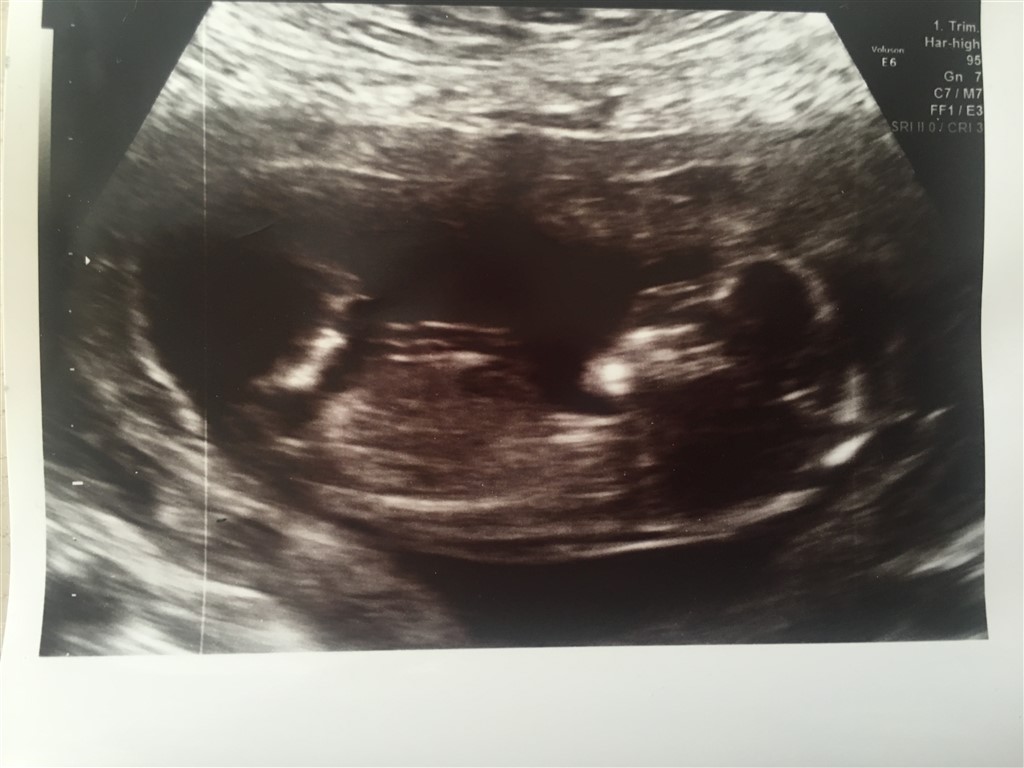

Må jeg spørge hvorfor? Eller er det bare en tanke? Jeg forstår nemlig ikke de streger man kigger efter

Ved en pige er der tre hvide streger, hvor den i midten er mindst, og minder om en burger.

ved drenge er der kun to streger.

giver det mening! ?